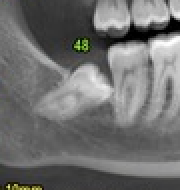

lesione nervo alveolare

BlogDente del giudizio

La lesione del nervo alveolare inferiore: considerazioni cliniche